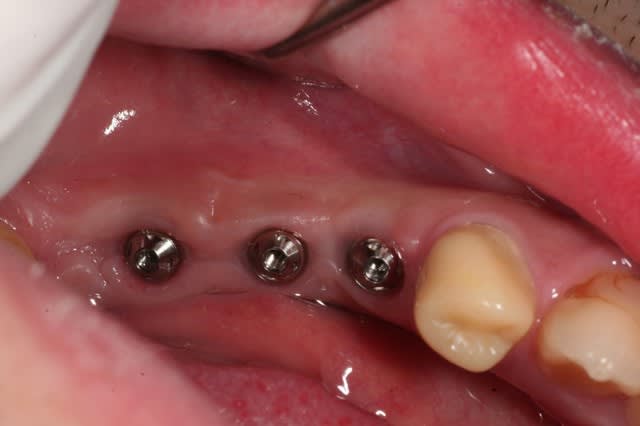

on continue avec ce cas...

ces quelques images ont pour but de dédramatiser la prothèse sur implants, et bien montrer que ce n'est pas pire qu'Ikéa...

alhoun

pour ceux qui ne sont pas familiers avec ce type de procédure, les questions sont les bienvenues.

est ce que tu solidarises tes transferts entre eux avant l'empreinte ?

tu ne protèges pas tes vis pour devisser plus facilement en pick up avec cire ou autre perso je mets de la cire d'ortho(celle pour éviter les blessures) qu'on enlève très facilement ?http://www.eugenol.com/eugenol/file.php?21,file=14295

quel matériau d'empreinte(DMG) ?

.

non, je ne solidarise pas sur une petite portée comme ça. quand c'est plus grand, je passe à l'empreinte au plâtre.

ici c'est du pentasoft, et si tu regardes bien, les têtes de vis sont accessibles pour le dévissage.